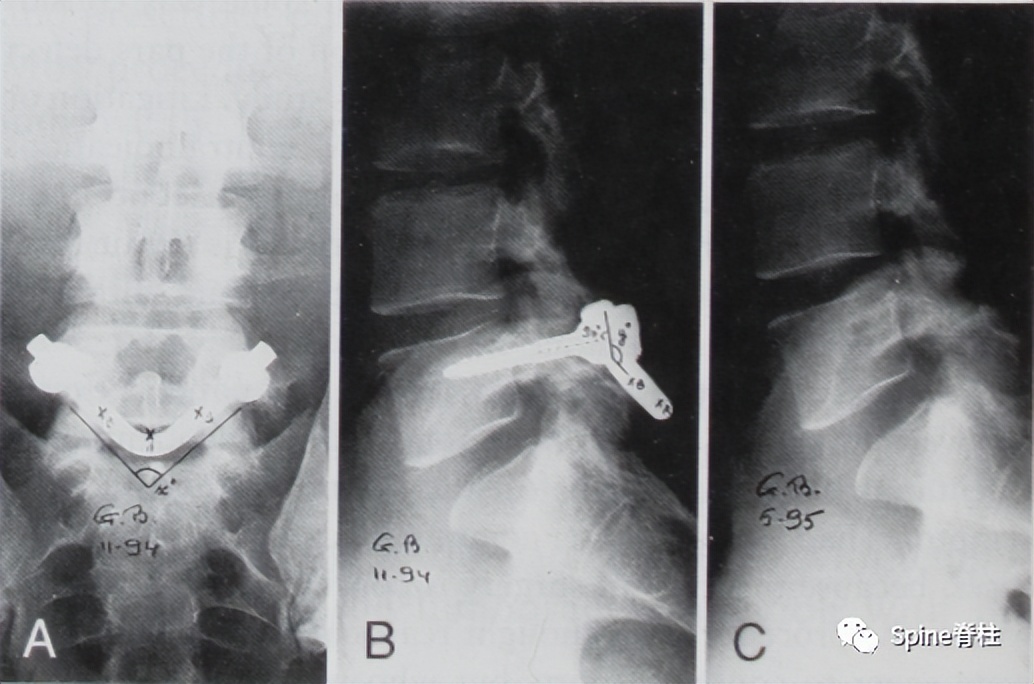

PMID: 9199377

PMID: 15699811

PMID: 17520298